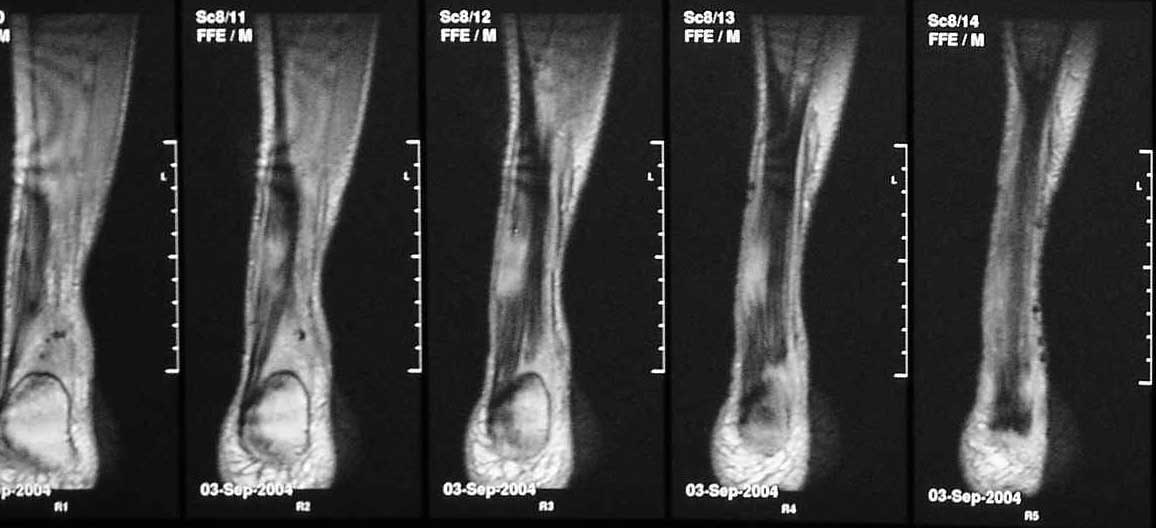

В сентябре сделана МРТ, цитирую заключение: "по внутренней поврехности сухожилия на уровне средней трети определяется очаг с неоднородной гиперинтенсивностью сигнала на T2W и изоинтенсивного сигнала T1W неправильной форму. Прротяженность очага до 43 мм в вертикальном диаметере. В центральной части очага на протяжении до 22 мм определяется прерыв и диастаз волокон ахиллова сухожилия. Заключение: Частичный дегенеративный разрыв ахиллова сухожилия, тендинит".

Что интересно, аналогичная МРТ-картина выявлена за месяц до операции. Однако в справке после операции ничего о разрыве нет.

Подобное решение основано на результате магнитно ядерного резонанса который показывает что разрыв сухожилия не превышает 50 процентов от общего диаметра